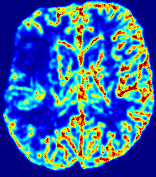

Slice #1Slice #2Slice #3Slice #4Slice #5Slice #6Dgtsuperscript𝐷gtD^{\text{gt}}Refer to captionRefer to captionRefer to captionRefer to captionRefer to captionRefer to caption(a)Refer to captionRefer to captionRefer to captionRefer to captionRefer to captionRefer to caption(b)Refer to captionRefer to captionRefer to captionRefer to captionRefer to captionRefer to caption(c)Refer to captionRefer to captionRefer to captionRefer to captionRefer to captionRefer to caption(d)Refer to captionRefer to captionRefer to captionRefer to captionRefer to captionRefer to caption(e)Refer to captionRefer to captionRefer to captionRefer to captionRefer to captionRefer to caption(f)Refer to captionRefer to captionRefer to captionRefer to captionRefer to captionRefer to captionRefer to caption000.060.060.060.120.120.120.180.180.180.240.240.240.300.300.30(mm2/s)𝑚superscript𝑚2𝑠(mm^{2}/s)

Figure 13: PIANO effectiveness and robustness testing: diffusion imaging via diffusion. Top row shows Dgtsuperscript𝐷gtD^{\text{gt}} used for simulating the ground truth pure diffusion. (a)-(f) refer to the results for D𝐷D estimated from the ground truth pure diffusion image time-series where Rician noise at levels 0%, 2%, 4%, 6%, 8%, 10% was added respectively.

Similarly, starting from the same initial condition C0superscript𝐶0C^{0} as in the ‘Advection Imaging’ experiment for each patient, we simulate concentration time-series {Cti(Ω)|i=0, 1,, 40}conditional-setsuperscript𝐶subscript𝑡𝑖Ω𝑖0140\{C^{t_{i}}\in\mathbb{R}(\Omega)|i=0,\,1,\,\ldots,\,40\} via a diffusion PDE, where we define the ground truth diffusivity D:=Dgtassign𝐷superscript𝐷gtD:=D^{\text{gt}} via the ADC map of the ISLES 2017 training set (ADC values are scaled by 0.000010.000010.00001 to ensure numerical stability):

Note this is likely not a spatially representative ground-truth for perfusion imaging, as it measures different effects from diffusion imaging. However, we still use it as a quasi-realistic pattern of diffusivity in the brain. We also added 2%, 4%, 6%, 8%, 10% levels of Rician noise to obtain simulations of ‘Diffusion Imaging’. The estimated Destsuperscript𝐷estD^{\text{est}} given concentrations of all noise levels for one patient are shown in Fig. 13, PIANO estimation results for all patients are summarized in Fig. 11 (b). Again, PIANO demonstrates its capability to recover the underlying diffusion field. In Fig. 13, when the noise level is increasing, some noisy patterns indeed appear in the associated Destsuperscript𝐷estD^{\text{est}}. Note that the ground truth diffusivity applied in this simulation experiment is about ten times larger than the diffusivity estimated in reality (Fig. 3, Fig. 4).